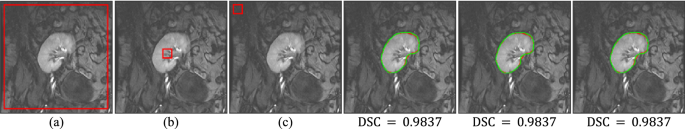

Moreover, to verify the robustness of the FML method to contour initialization, we use it to segment kidney on a group of images with different LS initializations (see Fig. 4): outside the kidney, inside the kidney, and totally far away from the kidney. It can be seen from the results in Fig. 4 that the FML method can consistently achieve the same high accuracy regardless of the position of the initial LS contour is in the image.

Segmentation results of the FML method on DCE-MRI image with three different LS contour initializations. (a–c) show DCE-MRI image with initial contours outlined in red. Last three columns show segmentation results of (a–c) in red while ground-truth segmentations are outlined in green, with DSC reported beneath each result.